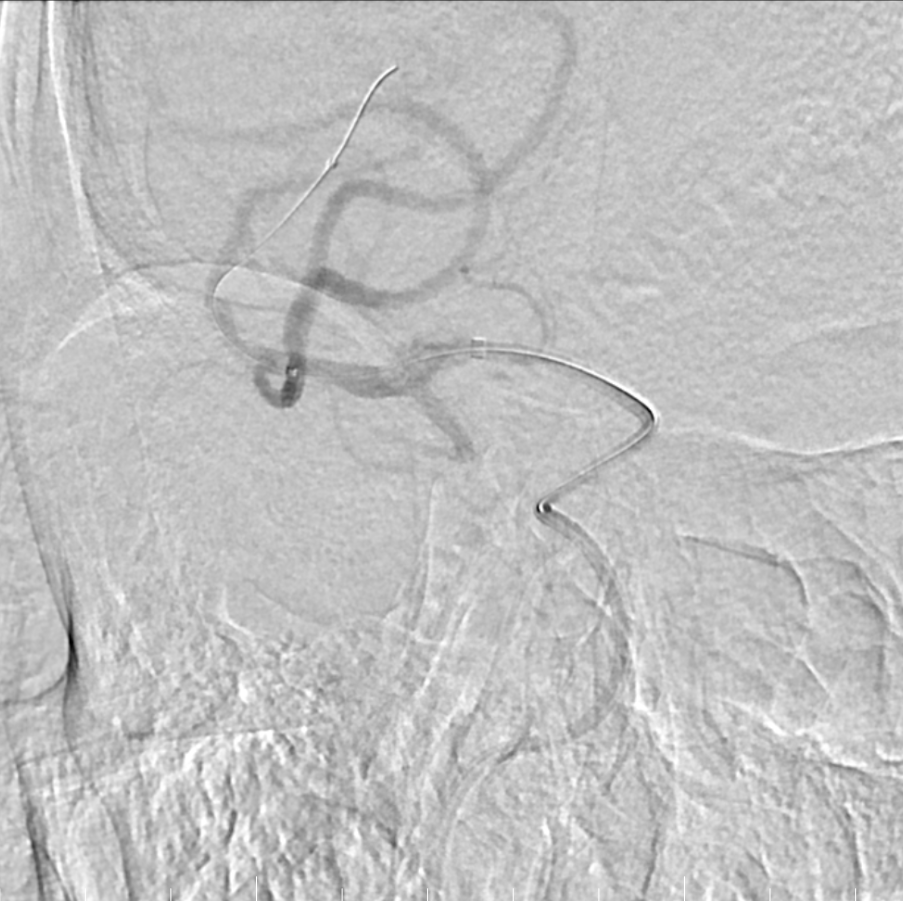

Tarvos微导丝轻松超选,到达M1段。

Tarvos微导丝携微导管到位。

支架释放,采用SWIM技术取栓。